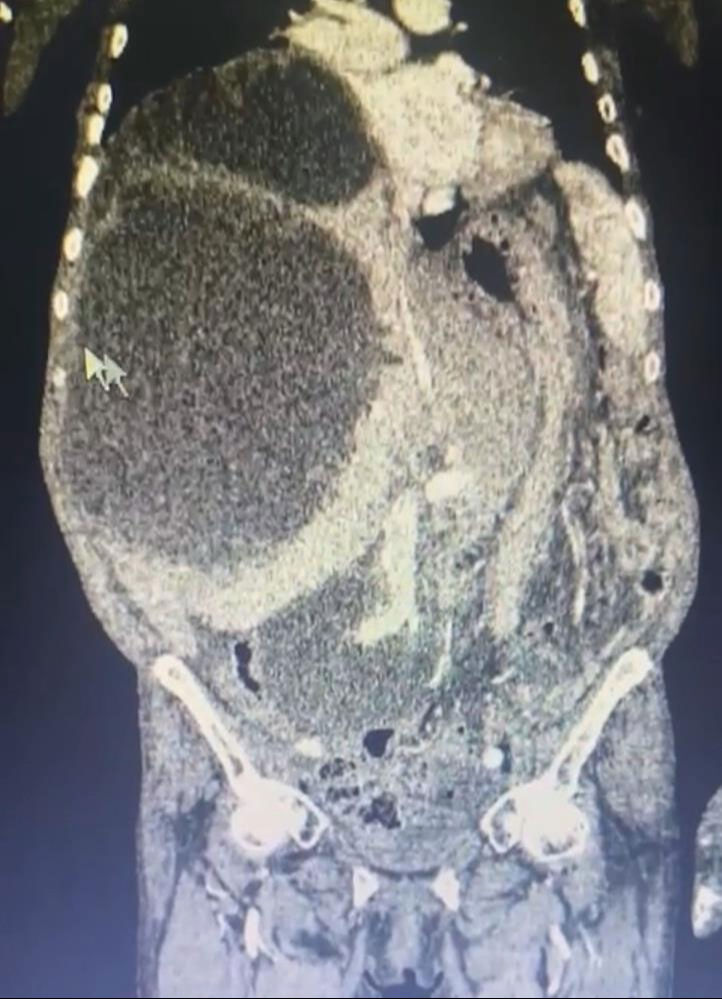

Trabzon’da eşi benzerine rastlanmayan bir operasyon gerçekleşti. Kistlerin büyüklüğü dikkat çekerken Genel Cerrahi Uzmanı Opr. Dr. İsmet Çelik, dünya literatüründe tüm karnı dolduran ve 90 santime ulaşan kist görmediklerini belirterek Taşdelen'e yapılan gerekli tetkikler ve görüntüleme sonucu karaciğerinde üç adet kedi-köpek kisti (hidatik kist) tespit ettiklerini ifade etti.

“Asiye Hanım, maalesef ihmal edilmiş bir hastamız. Bu kist, kedi ve köpeklerin dışkısı ve yediği yiyeceklerle bulaşan bir hastalık. Bu kist, genellikle tesadüfen yakalanabilir. Karaciğere yerleşir. Bu hastamızda da durum öyle olmuş. Ameliyat olamayacağı söylenip eve yollanmış. Bizler detaylandırıp ameliyat kararı aldık. Hastamızın karaciğerinde 3 ayrı kist vardı. Tüm karnı kist ile kaplıydı. 2 tanesinin tamamına çıkardık. Diğerini ise kontrolle alarak içini boşalttık. Dünya literatüründe tüm karnı dolduran ve 90 santime ulaşan kist görmedik.”